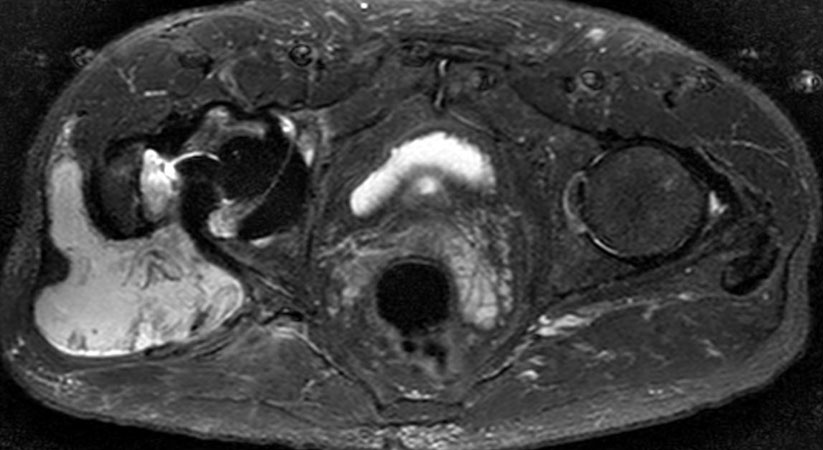

Hip imaging with metal implant using MARS at 1.5T

**Only for use with MR Safe or MR Conditional Implants by strictly following the Instructions for Use.